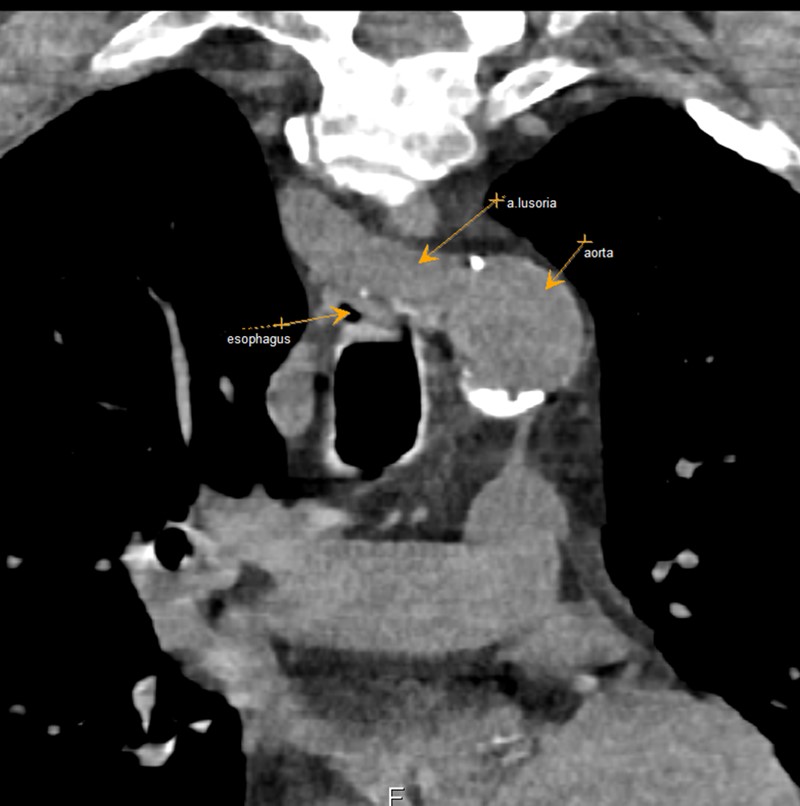

Рисунок 2 - Пациент А. 1955 г.р., корональная проекция КТ органов грудной клетки

Примечание: cтрелками указаны a. lusoria, отходящая от дуги аорты, пересекающая пищевод